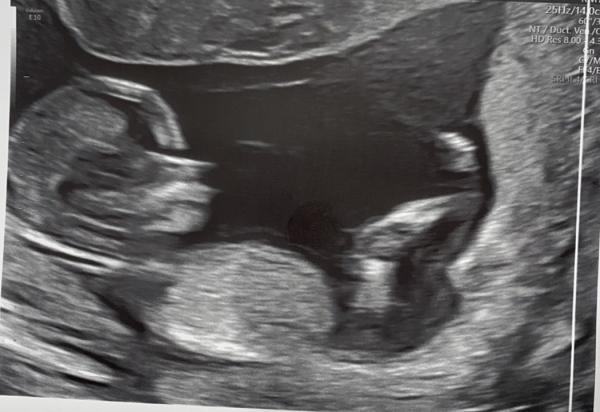

Hey ihr,  Ich hatte gestern mein ETS bei 13+1. Kennt sich jemand mit der Nub Theorie aus und kann eine Tendenz fürs Geschlecht abgeben? Ich würde mich total über eure Meinung freuen.

Bild zu Junge oder Mädchen, kann jemand helfen? - Schwanger - wer noch? Rund um die Schwangerschaft

Guten Morgen Mama19.21,  leider ist auf deinen Bildern der Nub nicht mit drauf. Drücke dir aber die Daumen, dass die Zeit schnell vergeht und ihr bald wisst, was es ist 🥰 Liebe Grüße